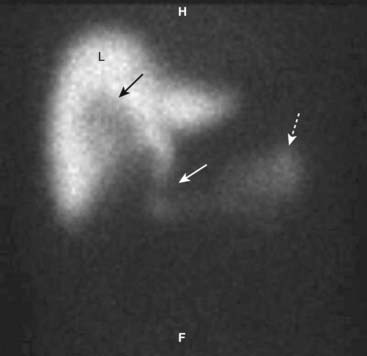

image Radionuclide scans (HIDA scans) are also used in the diagnosis of acute cholecystitis.

Hepatoiminodiacetic acid (the “HIDA” in HIDA scan) is tagged with a radioactive tracer (Technetium Tc 99m), injected intravenously and imaged with a special camera after it has been excreted by the liver into the bile and emptied into the small intestine.

In patients with obstruction of the cystic duct, the tracer will not appear in the gallbladder. In patients with obstruction of the common bile duct, the tracer will not appear in the small intestine. Either finding usually is caused by an obstructing gallstone (Fig. 19-6).

Figure 19-6 HIDA scan in cystic duct obstruction.

HIDA, a radioactive labeled isotope, concentrates in the liver (L) and is then excreted into the biliary ducts. On this delayed image, the common bile duct (solid white arrow) and small bowel (dotted white arrow) fill normally because the common bile duct is patent. The cystic duct and gallbladder do not fill because the cystic is obstructed, by a stone in this case. There is a tracer-free (photopenic) area in the gallbladder fossa because the nuclide cannot fill the gallbladder lumen (solid black arrow).